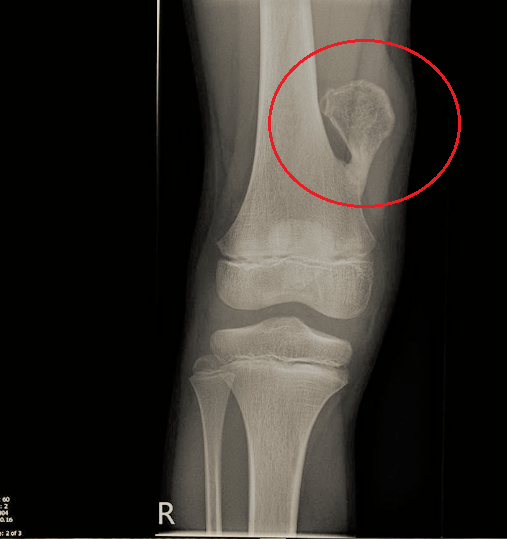

Rider’s bone o “osso del cavaliere”, sta ad indicare un’escrescenza ossea di natura benigna che si genera a lato del femore. Ma perché “del cavaliere”?

Il corpo, in risposta, genera e deposita più calcio vicino ai tendini per rinforzarne la struttura ossea e col tempo questo calcio va ad ossificarsi causando la formazione di una esostosi o protrusione ossea.

Queste esostosi possono verificarsi in altre parti del corpo, ma questa del femore in particolare è così chiamata perché in passato si osservava nei soggetti che montavano a lungo a cavallo.